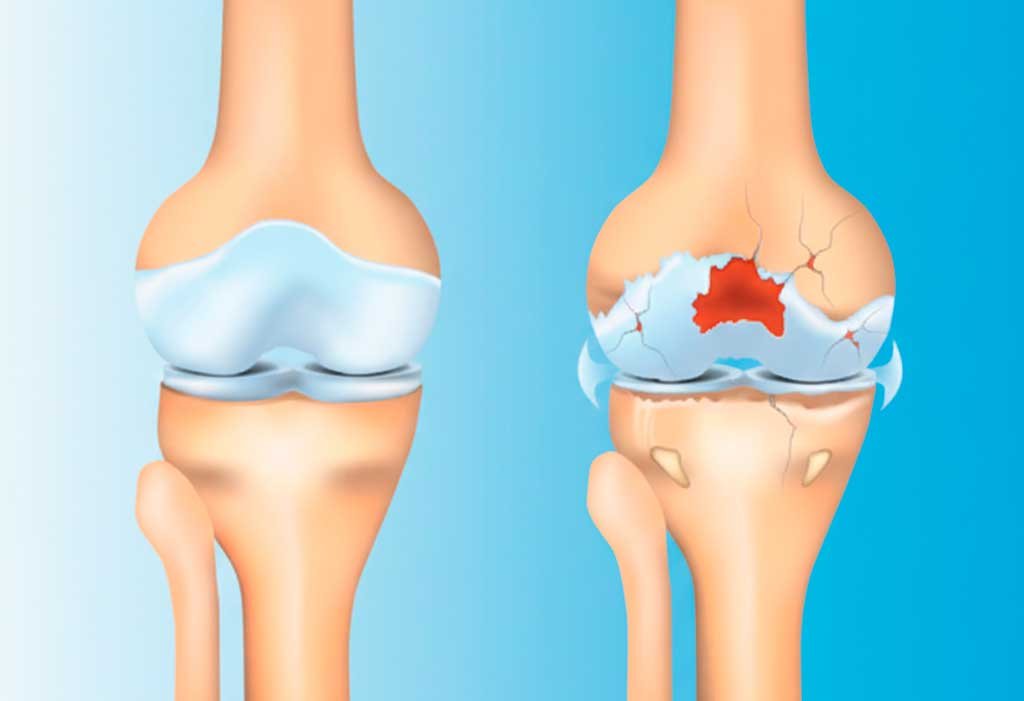

Primeiramente, a artrose é processo degenerativo que afeta a cartilagem articular do joelho. Essa cartilagem funciona como amortecedor natural, permitindo movimento suave e sem atrito entre os ossos. Consequentemente, quando ela se desgasta, os ossos começam a friccionar diretamente, causando dor, inflamação e rigidez.

Ademais, a artrose não afeta apenas a cartilagem. Com a progressão, há alterações nos ossos subjacentes, formação de osteófitos (bicos de papagaio), espessamento da cápsula articular e inflamação da membrana sinovial.